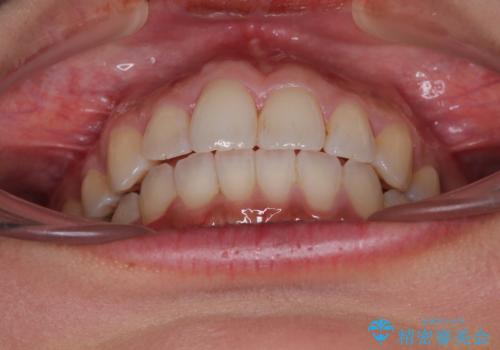

前歯のデコボコを改善 インビザラインの矯正治療

上下顎ともに歯列全体の後方移動とIPR(歯と歯の間を削る)によってデコボコが解消するように設計し、インビザラインにより治療を行うこととしました。

下顎前歯は後戻りを起こしやすいため、舌側を細いワイヤーで固定し、マウスピース型リテーナーで保定を行うこととしました。